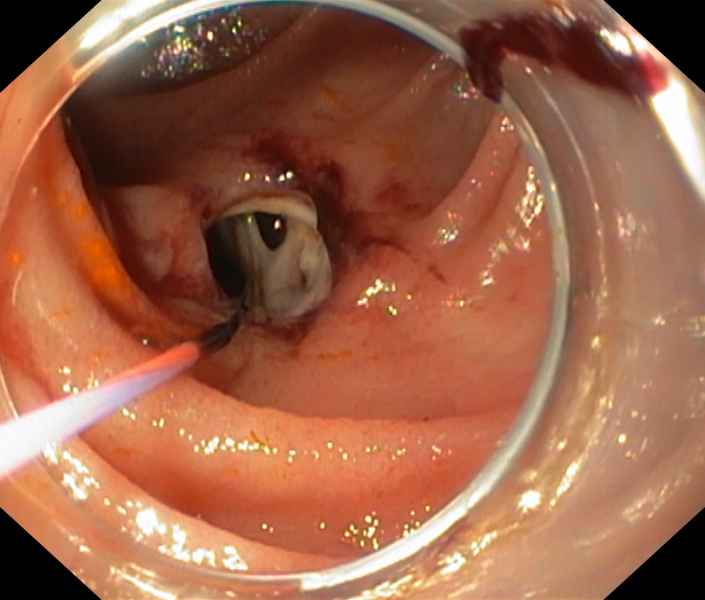

Paracolic intra-abdominal abscess diagnosed and treated through colonoscopy

Fotografia